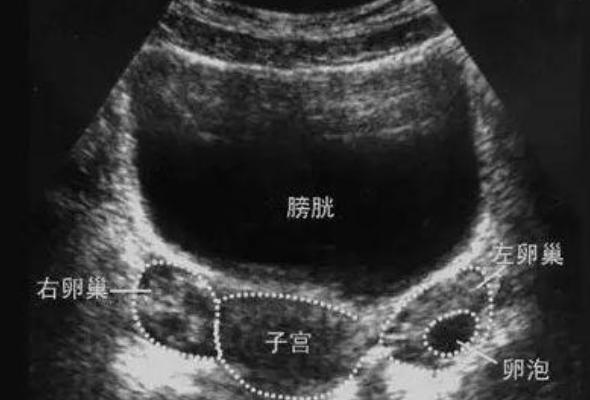

3. 卵巢B超:看“基础盘子”够不够大

B超是另一项关键检查,最好在月经第2-3天进行。为什么要选这个时间?因为这时卵泡刚起步,最能看清真实的基础数量。我们通常会数基础窦卵泡(AFC)的数量,并观察卵巢结构和子宫内膜情况。

如果基础卵泡数量多,说明卵巢潜力大;数量少,就要考虑用药难度和取卵可能性。这一步就像是“盘点仓库”,仓库里货物多,后面操作自然灵活;货物少,就得格外精打细算。